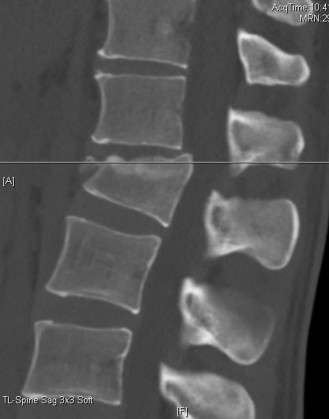

Initial trauma radiographs demonstrated a loss of anterior and middle column height at L1, with a focal kyphotic deformity. However, plain films are vastly insufficient for definitive surgical planning in thoracolumbar trauma. A high-resolution, fine-cut Computed Tomography (CT) scan of the entire spine was obtained. The CT images confirmed an L1 burst fracture with severe comminution of the vertebral body. Sagittal and axial reconstructions revealed 50% canal compromise secondary to a large retropulsed bone fragment originating from the posterosuperior aspect of the L1 vertebral body. Furthermore, the CT demonstrated 25 degrees of segmental kyphosis measured from the superior endplate of T12 to the inferior endplate of L1.

A critical finding on the axial CT slices was a vertical, split fracture propagating through the L1 lamina. This is a highly significant morphological feature. A lamina fracture in the setting of a burst fracture with retropulsion strongly correlates with a dural tear and potential entrapment of the cauda equina nerve roots. When the vertebral body bursts posteriorly, the pedicles are driven outward, and the lamina fractures as the spinal canal attempts to expand to accommodate the retropulsed bone. If the dura is lacerated, nerve roots can herniate through the dural defect and become incarcerated in the laminar fracture site.